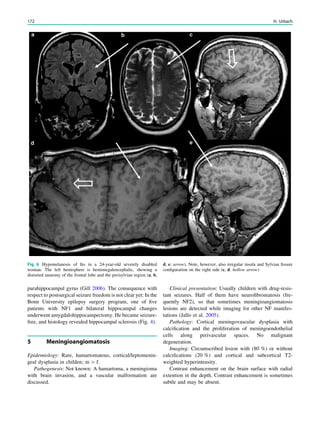

Fig. 2 Dural a. v. fistula. A 53-year-old man presented with two tonic–

clonic seizures. MRI shows circumscribed edema in the left frontal lobe

(a, hollow arrow) and an abnormal vessel running in the left sulcus

rectus (c, arrow). The digital subtraction angiogram of the left internal

carotid artery shows a frontobasal dural arteriovenous fistula fed via

ethmoidal arteries (d, arrow) and confirms the abnormal vessel as a

draining vein (e, arrow)